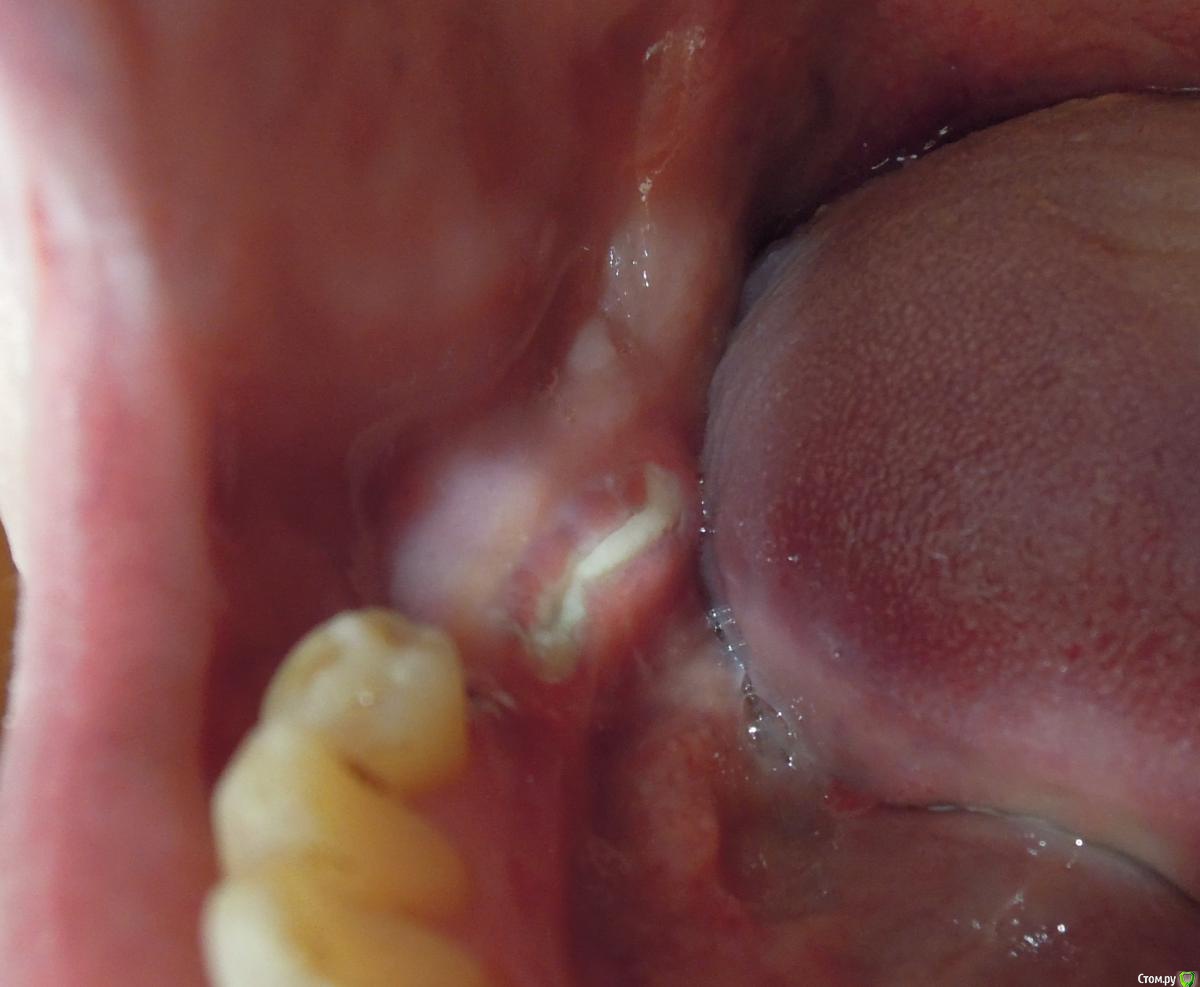

Шприков Опубликовано 30 октября, 2018 Поделиться Опубликовано 30 октября, 2018 Всем привет.Вот уже прошел месяц, как мне сделали синус лифтинг и вкрутили три импланта 5, 6, 7.Только вот кость никак не затягивается десной, хожу с такой костью уже 3 недели.Почему так получилось?Когда зарастет и заростет ли вообще?Что делать?Спасибо. Ссылка на комментарий

Шприков Опубликовано 30 октября, 2018 Автор Поделиться Опубликовано 30 октября, 2018 Короче, разрезали кость и раздвинули, вкрутили импланты, в разлом кости насыпали костную ткань, потом все зашили.Через четыре дня, смотрю торчит имплант, опять зашили, через два дня, смотрю торчит кость, вот так и торчит уже 3 недели.Врач говорит, жди заростет.) Жду.) Ссылка на комментарий